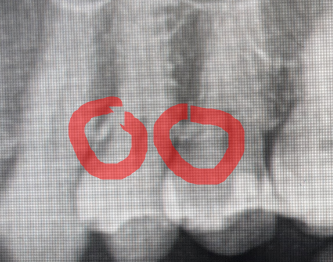

Стоматологи тут? Говорят что надо ЧИСТИТЬ КАНАЛЫ у семёрки и ставить коронку. Нюанс в том что зуб не

Стоматологи тут?

Говорят что надо ЧИСТИТЬ КАНАЛЫ у семёрки и ставить коронку.

Нюанс в том что зуб не болит. В январе с него отвалилась пломба, видно там чуть-чуть чёрное, но никак не беспокоит (поэтому так долго не шёл к врачу).

Как думаете, развод? Ведь после удаления нерва зубу пизда через пару лет и нужно будет уже делать имплант.

Ещё смущает что снимок мне на руки не дали и никакого заключения не написали.

Пикрил мой. Сегодня только снимок делали, лечить записался на среду

я так понимаю ты про нижнюю семерку - тогда там еще и в кривизне каналов проблема может быть, но то такое

Пульпы мало, если не почистить каналы есть большой шанс, что зуб будет чувствительный после пломбы

Судя по снимку можно снять старую пломбу, если есть кариес убрать его и сделать керамическую вкладку Е.мах. Типа пломба керамическая, делает стоматолог-ортопед. Депульпировать думаю не стоит, но надо во рту смотреть.

Верхнюю или нижнюю? Хотя я бы , руководствуясь имеющейся информацией, обе попытался сохранить с нервами.

Возьмерку надо удалять, но у тебя на верхней смерке то же , скорее всего кариес. Но я не верен тк 2д рентен вообще говно для диагностики и если тебе диагнозы ставят не сделав кт-я бы наверное пошел в другую клинику